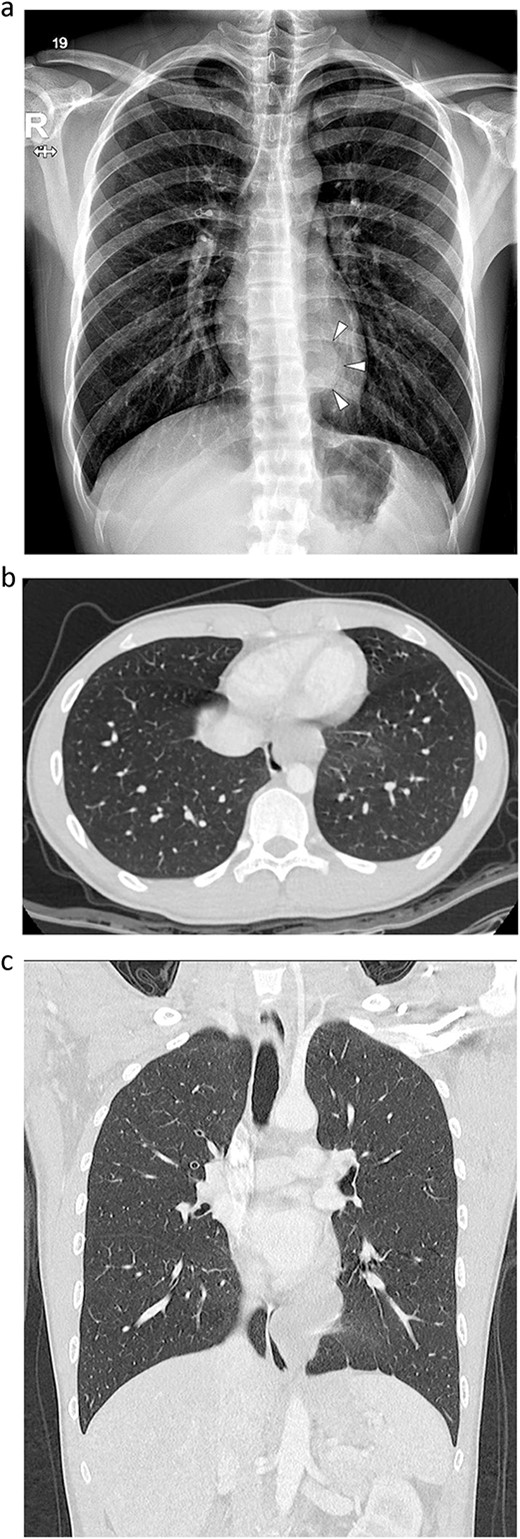

An 18-year-old male patient presented to the emergency department with right-side chest pain of 1-day duration. A plain chest x-ray confirmed a right pneumothorax. A tumor in the left lower paravertebral area was suspected (Fig. 1a). A CT of the chest was performed and showed a 6-cm large, well-defined, probable cystic mass in the left posterior mediastinum, adjacent to the esophagus. Esophageal duplication or bronchogenic or neurenteric cyst was suspected (Fig. 1b and c). The patient was discharged after pneumothorax had improved. Two months later, he was readmitted for surgery to remove the cystic tumor. Single-incision video-assisted thoracoscopic surgery (VATS) was performed to treat the posterior mediastinal tumor. The patient was placed in the prone position. An incision of 4 cm in length was made in the left ninth intercostal space at the lateral line of the scapula. A 5-mm thoracoscope with a 30-degree view was used. A cyst was identified in the posterior mediastinum (Fig. 2a), and a longitudinal incision was made in the mediastinal pleura. The left vagus nerve was placed beside the tumor. The lower half of the cystic mass was embedded in the muscular layer of the esophagus (Fig. 2b) and was in contact with the esophageal mucosa. The cyst was dissected carefully from the surrounding tissue. During dissection, the cyst ruptured, discharging an ivory mucoid creamy fluid. The cyst was completely removed with no injury to the esophageal mucosa. The esophageal mucosa, which was in close contact with the cyst, was stretched and protruding. To cover the exposed esophageal mucosa, the dissected esophageal muscle and periesophageal tissue were approximated with a continuous suture using a barbed suture (V-Loc™ 90, Medtronic) (Fig. 2c). Another barbed suture was used to repair the mediastinal pleura. A 24-Fr chest drain tube was placed through the same port (Fig. 2d). The operation took 80 min. The patient’s diet was started on the evening of the surgery. The chest drain was removed on the 1st postoperative day, and the patient was discharged from the hospital on the 2nd postoperative day without problems. Histopathological examination revealed a bronchogenic cyst. A CT scan of the chest carried out 2 years 7 months after the operation and confirmed that the patient had healed without any complications (Fig. 3).

Radiographs of an 18-year-old man. (a) Simple radiograph shows a tumor in the left lower paravertebral area (arrow head). (b, c) A contrast-enhanced computed tomography scan. A 60 × 36 mm well-defined lobulated cystic mass in the left posterior mediastinum, abutting the esophagus.